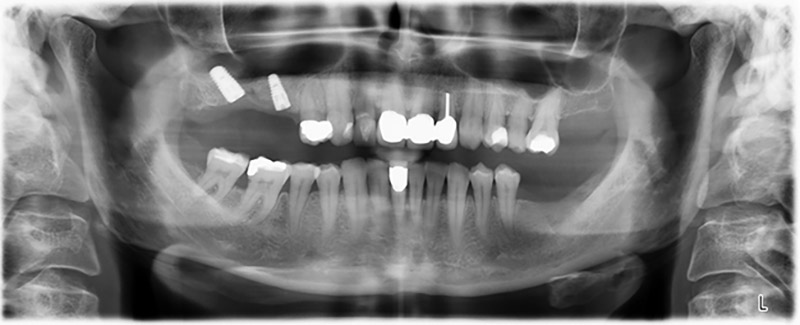

Etwa sechs Monate nach Extraktion der Zähne 16 und 14 wurde zur Planung und Risikominimierung eine digitale Volumentomografie (DVT, Planmeca) erstellt. Hierbei wurde deutlich, dass der Knochen sich nicht in der gewünschten Quantität regeneriert hat (Abb. 2 bis 7).

Um eine festsitzende Versorgung auf mindestens zwei Implantaten zu gewährleisten, ist eine Sinusbodenelevation sowohl in Regio 16 als auch in Regio 14 erforderlich. Da in diesem Fall das Restknochenangebot extrem gering ist, müsste ein verhältnismäßig großer Knochenaufbau durchgeführt werden. Große Knochenaufbauverfahren sind invasiv, mit einer höheren Patientenmorbidität verbunden, zeitintensiv und kostspielig. Die Vorhersagbarkeit der Behandlungsresultate ist geringer und das Misserfolgsrisiko höher. Vor dem Hintergrund dieser Nachteile, wurde die Patientin über eine herausnehmbare Alternative aufgeklärt, die sie jedoch konsequent ablehnte.

Um die Augmentation auf Regio 14 einzuschränken, wurde in Absprache mit der Patientin eine Schrägstellung des Implantats 16 nach dorso-kranial geplant (Abb. 8).